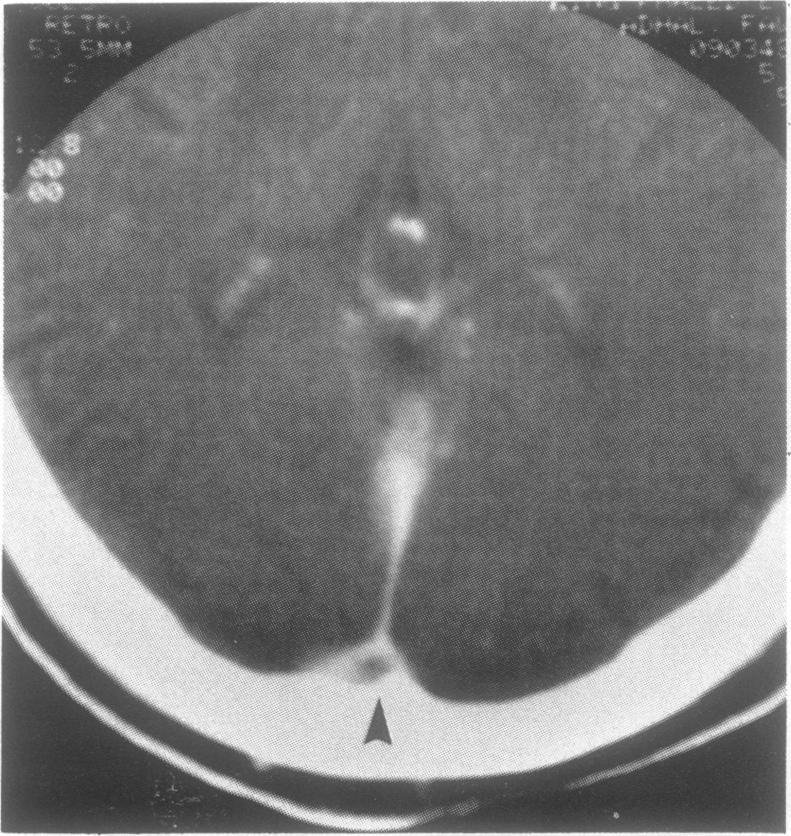

Behçet's disease is a multisystem disease characterised by the clinical triad of oral ulcers, genital ulcers and uveitis. Nervous system involvement is frequent and occasionally precedes other manifestations. Behcet's disease is not frequently considered in the differential diagnosis of papilloedema. We report four cases of Behcet's disease in which papilloedema occurred with or without dural sinus thrombosis. MRI is of great value in the investigation of such patients as it can demonstrate venous sinus thrombosis non-invasively or suggest the diagnosis by showing the associated parenchymal lesions secondary to small vessel pathology.